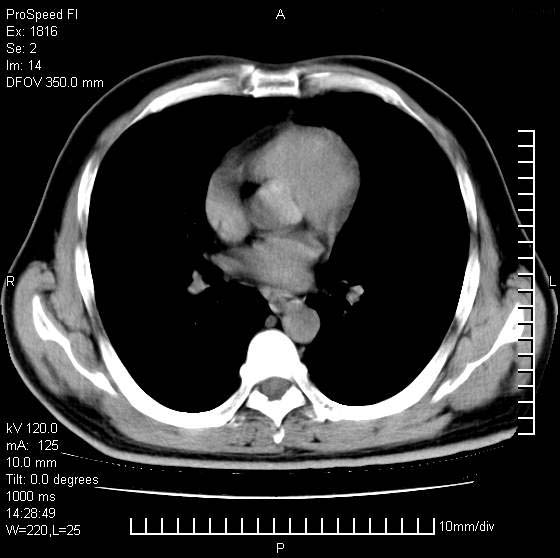

男性,50 ,肺结核9年,咳嗽,胸痛一周。右上肺见一厚壁空洞,周边有点样钙化,胸膜牵拉,洞壁较光整。诊断结核性空洞。有癌性的可能吗? 余肺野无异常,没有上传。

洞壁较厚内壁比较光整,两个病灶有关联性,纵隔淋巴结不大,考虑结核性空洞。

9年的结核应该呈现多形态病灶,该病例只能见到少许纤维索条影,似乎与结核的演变不太相符。空洞内壁不光整,外侧伴有胸膜粘连,考虑癌性空洞可能性大,期待结果。